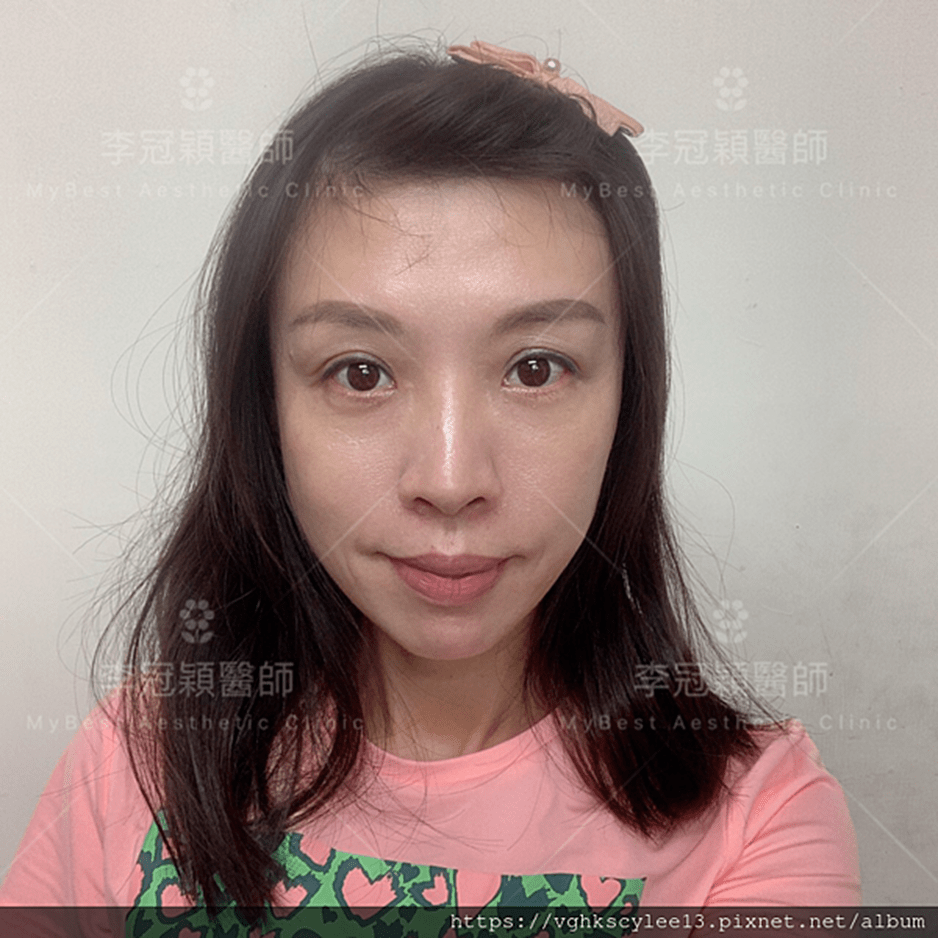

範例:以為要削骨,經內視鏡客製化太陽穴墊片,改善臉骨過大問題。也提升臉部對稱。

前 後(三個月)太陽穴到側額凹陷,眼尾下垂。(太陽穴不對稱往往來自顴骨大小不對稱)可以調整改善對稱性。

臉型不對稱 在太陽穴有一定落差,上圖經過太陽穴墊片矯正後,也明顯改善不對稱的視覺效果。重要的一點可以支撐眼尾下垂,改善老態眼神!(上圖)經內視鏡墊太陽穴跟提眼尾術後滿意。

範例:先天臉型不對稱,經太陽穴墊片手術改善。